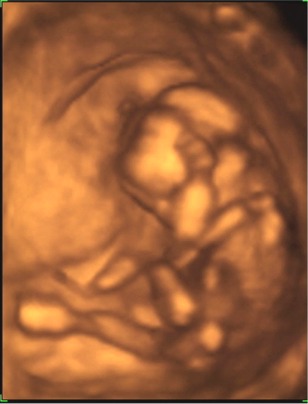

Megjöttünk a 4D-ről :) :) :)

Nagyon nagyon jó volt! Csúcsszuper :D

A babucim iszonyú jól érzi magát odabent, fészkelődik, rugdalózik megállás nélkül, ugyanúgy mint a 12 hetesen :lol:

Fejétől a lábujjáig 13cm .. persze ennél kisebb helyet foglal, mert fel van húzva a lába ..stb.

10,2 dkg a Lelkem :)

Láttuk a kis szívét, a 4 szívkamrát, az agyát... az agyféltekéket, a gyomrát, a húgyhólyagját .. szóval messze felülmúlta a vizsgálat minden várakozásunkat.

A csöppség nemét nem merték biztosra mondani, így ezzel kapcsolatban még izgulhatunk kicsit :lol: :lol:

A 2D alapján kislányt mondanának .. de a 4D-n néha láttunk gyanus elemeket. De az lehetett a szeméremajkak is .. mert ebben az időszakban még azok is csúcsosak :) nah majd kiderül időben :) A nő szerint ebben az időszakban még nem lehet 100%-osra mondani, ő nem szeret jósolgatni.

A pici hasamnak viszont megvan az oka .. a hátrahajló méhem egy dolog, de abban is leghátul, lent a medencémben fészkelte be magát a babuci, így egészen a szeméremcsontomhoz kellett bekukkantanunk .. és nagyon nehezen tudtuk őt követni. De szerencsére egyfolytában mozgott .. így mindenét meg tudtuk nézni, és elkaptunk nagyon jó pillanatokat!

A kiskönyvemben április 9re vagyok kiírva, ha a hosszú ciklust belekalkulálom, akkor április 13. Na az első UH-n április 19-et mondtak (ez 8 hetesen volt), aztán a 12 hetesen április 13-at, most pedig április 14-et :) :) Nagy különbségek nincsenek, így rendben fejlődik a Drága!!!!

Boldogság van!!!

Mindjárt megpróbálok fotót mutatni róla!

Kép \"mutatom az arcocskám\"

Kép \"vakarom a fejecském\"

Kép \"látjátok hogy tornázom?\"

Kép \"elfáradtam ... hátrabújok pihenni\"